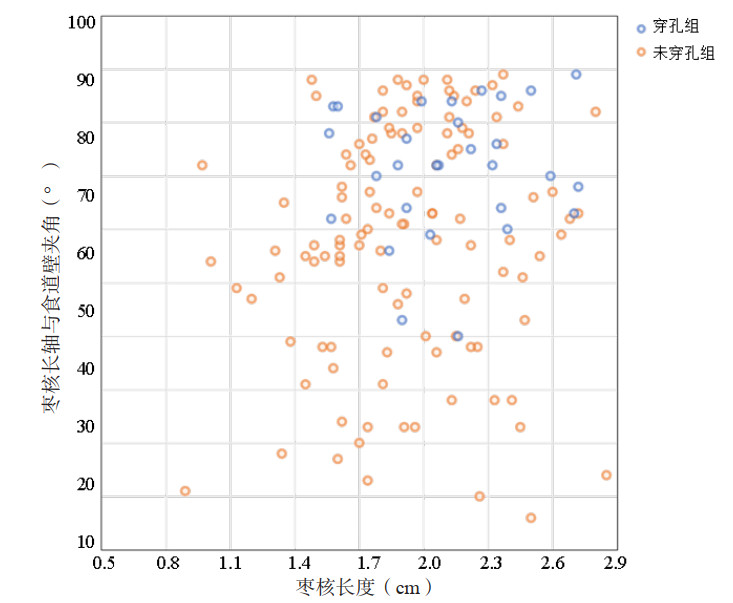

2 结果研究期间收集的食管枣核异物患者共计145例,其中穿孔组共30例,未穿孔组共115例。其在枣核长度、枣核长轴与食道壁夹角的坐标平面分布见图 2。

| 图 2 穿孔组(n=30)与未穿孔组(n=115)枣核长度、枣核长轴与食道壁夹角的坐标平面分布图 |

未穿孔组与穿孔组间的枣核长度数据、枣核长轴与食道壁夹角数据的差异均有统计学差异(均P < 0.05),如表 1所示。枣核长度数据中,未穿孔组的均值比穿孔组的均值小0.2 cm;枣核长轴与食道壁夹角数据中,未穿孔组的均值比穿孔组的均值大13.95°。